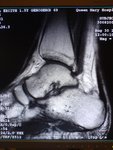

RadioEdric :: 我是白老鼠廿幾號 - 瑪麗醫院新裝之 3T 磁力共振掃瞄器